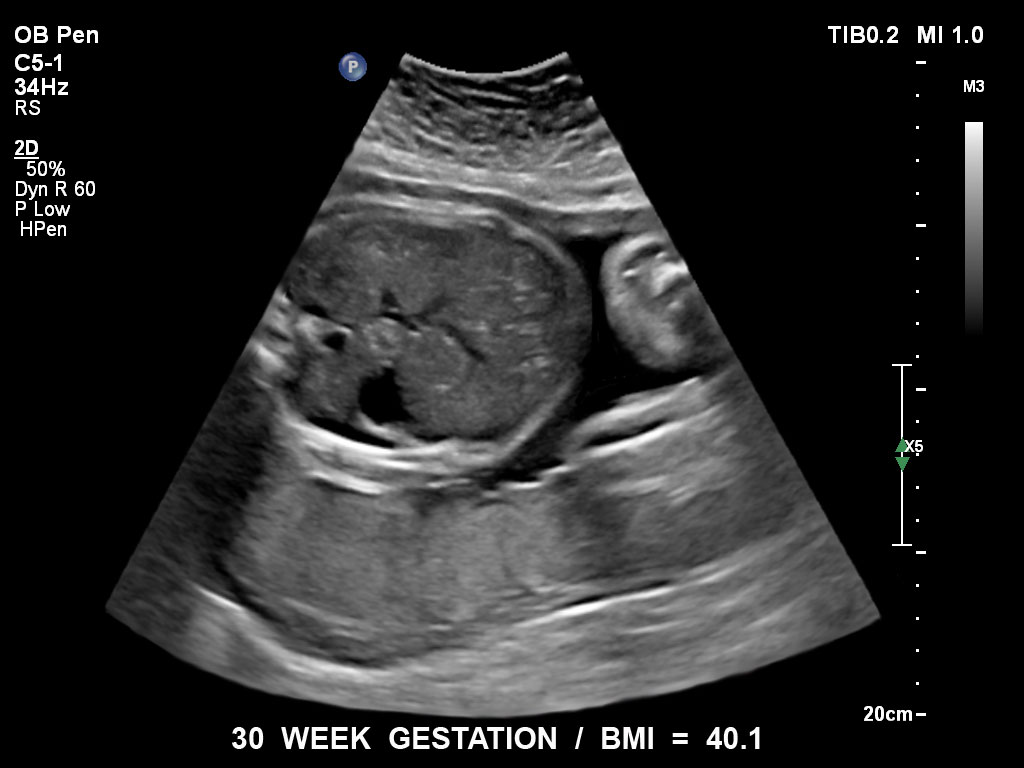

Überzeugende Bildgebung in allen Schwangerschafts­dritteln

Die EPIQ-Produktreihe mit ausgereiften Schallköpfen erfüllt die Anforderungen auch Ihrer anspruchsvollsten gynäkologischen Untersuchungen und während der gesamten Schwangerschaft.

• C5-1 PureWave-Breitband-Convex-Schallkopf für hohe Eindringtiefen in der Gynäkologie und der Geburtshilfe, für Patientinnen mit Schwangerschaftsdiabetes oder vorzeitigem Blasensprung